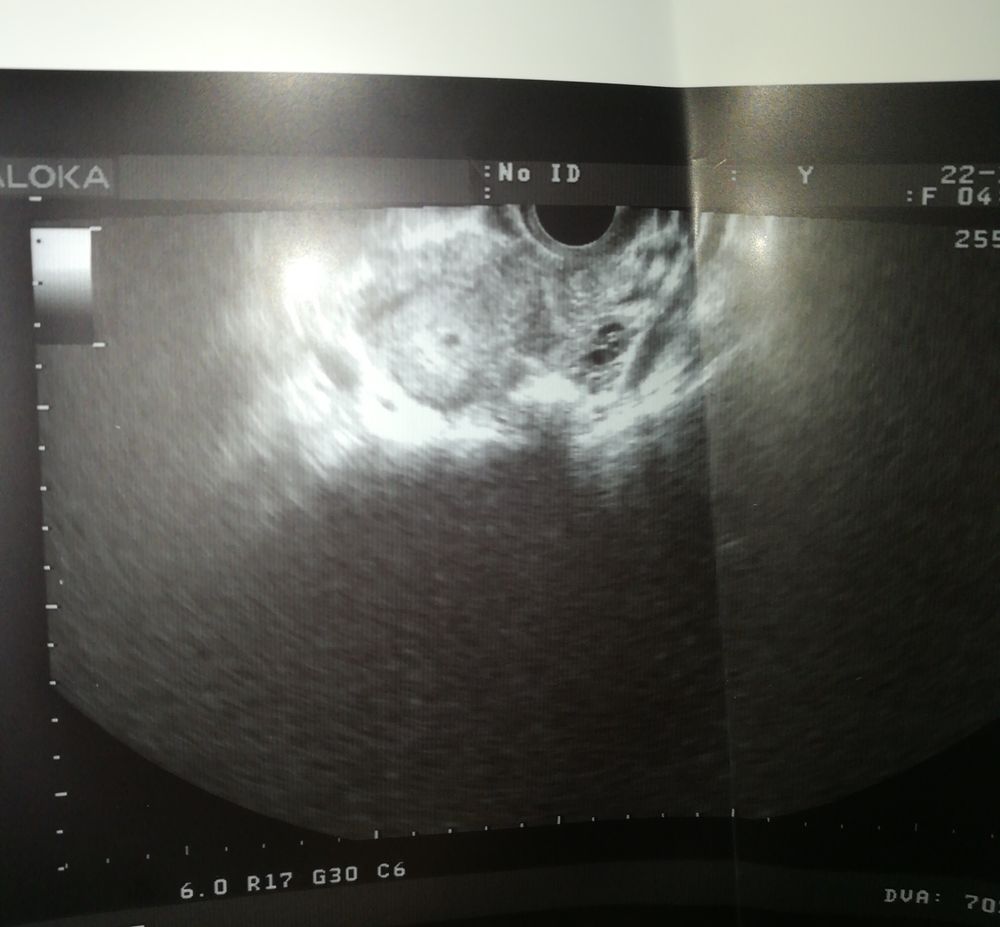

Я так понимаю, плодное яйцо, это вот точка где. А может кто понимает, справа, что это тогда?) Без тапок пожалуйста, ничего не объяснили, только срок и размер плодного яйца сказали)